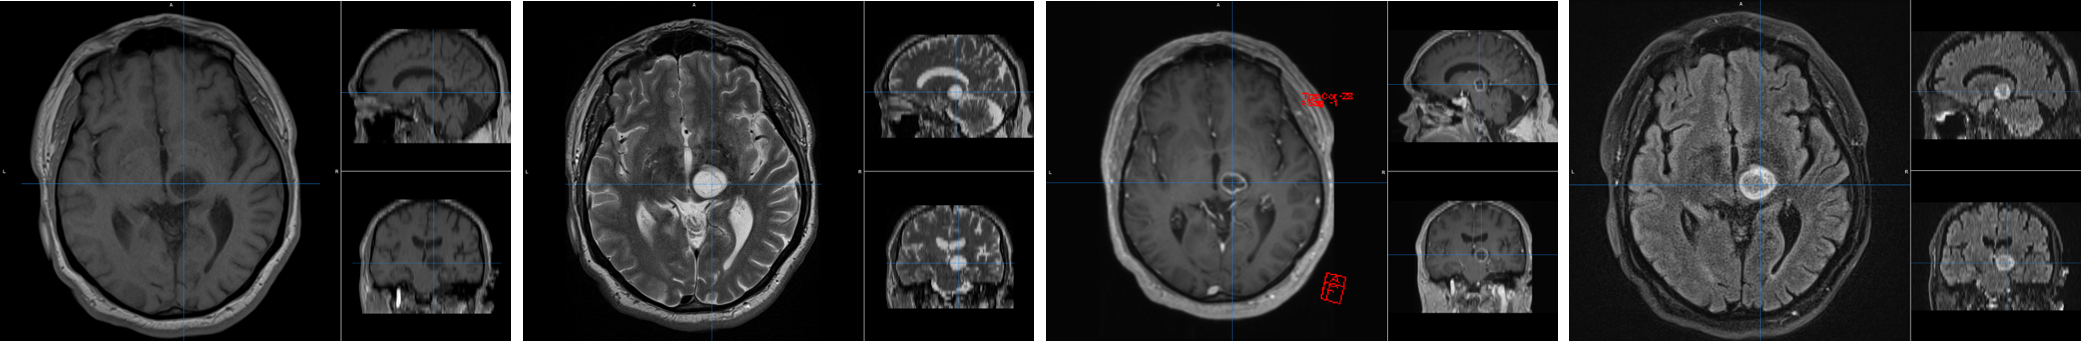

In Belgium, 800 people are diagnosed with a primary brain tumour each year. Their life expectancy depends strongly on the tumour type, and ranges from several decades for low-grade tumours to only about one year for the most malignant types. An accurate pathological diagnosis is therefore of primary importance. In clinical practice the workflow from initial consultation to therapy involves many steps within a multidisciplinary team of radiologists, neurosurgeons, neuropathologists, nuclear medicine professionals, radiotherapists, etc. In each step of this pipeline, there is a degree of subjectivity involved in the decision process. However, in literature there is growing evidence that a quantitative, and thus objective, approach can yield a correct diagnosis and therapy prediction. The goal of this project is therefore to investigate how a quantitative analysis of medical images (both MRI and PET) can contribute to a personalised medicine. In this project, we will implement a method for automated brain tumour diagnosis, using textural analysis in combination with other quantitative tumour parameters, such as volume, shape and histogram features. Using advanced classification algorithms, such as Support Vector Machines or Convolutional Neural Networks, an algorithm for automated diagnosis will be implemented.